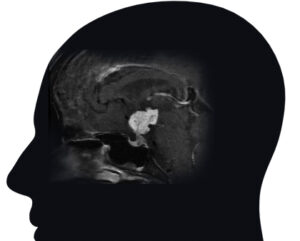

Craniopharyngiomas are typically diagnosed on MRI or CT scan, and are usually distinguishable from the more common pituitary adenomas, Rathke’s cleft cysts and meningiomas that might occur in the region around the pituitary gland and skull base. Craniopharyngiomas typically have both solid and cystic (fluid-filled) components, and many have calcification as seen on CT scan. Complete pituitary hormonal testing is also essential given that a majority of patients will have hormonal deficits. Similarly, most patients will need formal visual field and acuity testing to assess the impact of the tumor on vision and eye movements.